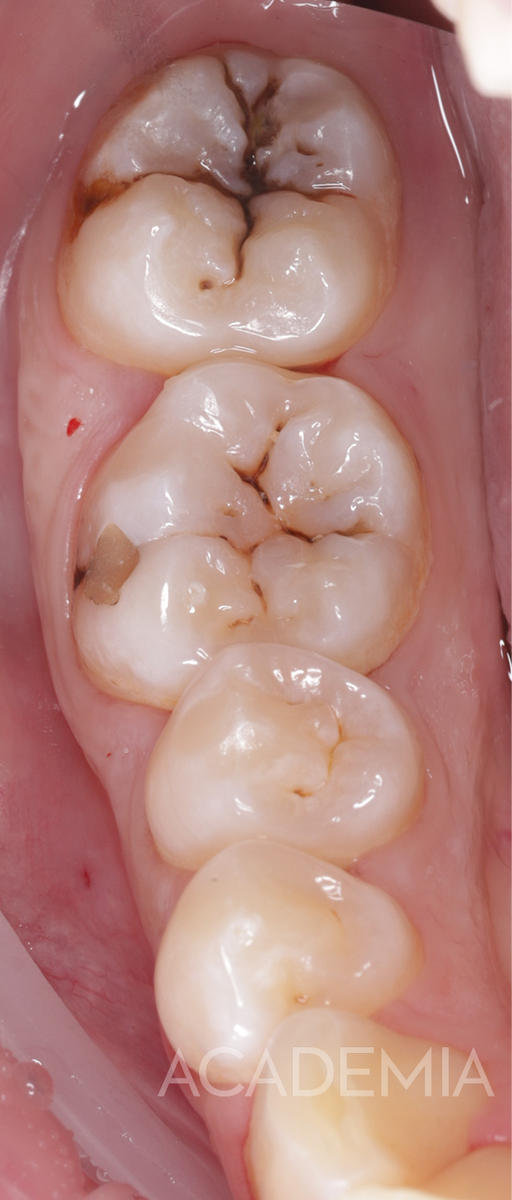

Как распознать глубокий кариес

Вот основные признаки, на которые стоит обратить внимание:

• ощутимая полость в зубе (часто темного цвета),

Как проходит лечение глубокого кариеса

Лечение глубокого кариеса зубов требует максимальной аккуратности.

Задача врача — удалить все ткани, пораженные кариесом, и при этом не вскрыть пульповую камеру, в которой находится нерв.